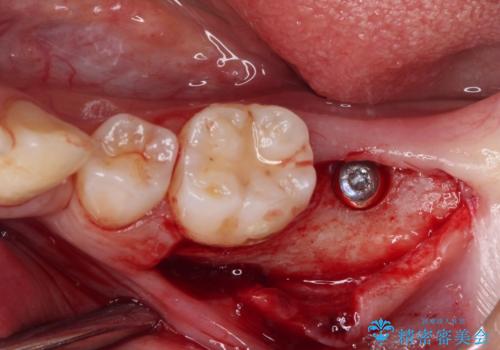

左下の欠損部は、世界中で高い信頼を得ているストローマンインプラントを用いて治療を行うこととしました。

まず生活歯髄療法を行い、その後部分矯正やインプラント処置を行いましたが、最初の処置から1年以上経っても右下奥の処置歯の神経組織に異常は認められませんでした。

部分矯正を行ったことで、違和感のない咬み合わせを達成することができました。